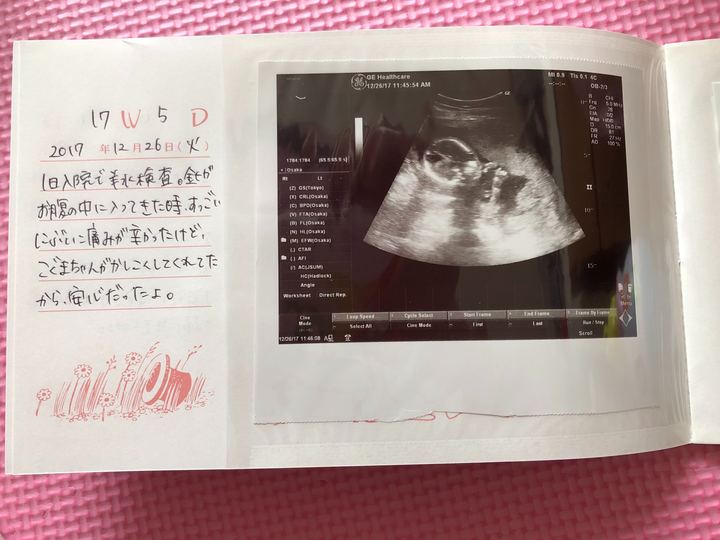

当時の心境を綴ったメモ

当時の心境を綴ったメモがありますので公開します。